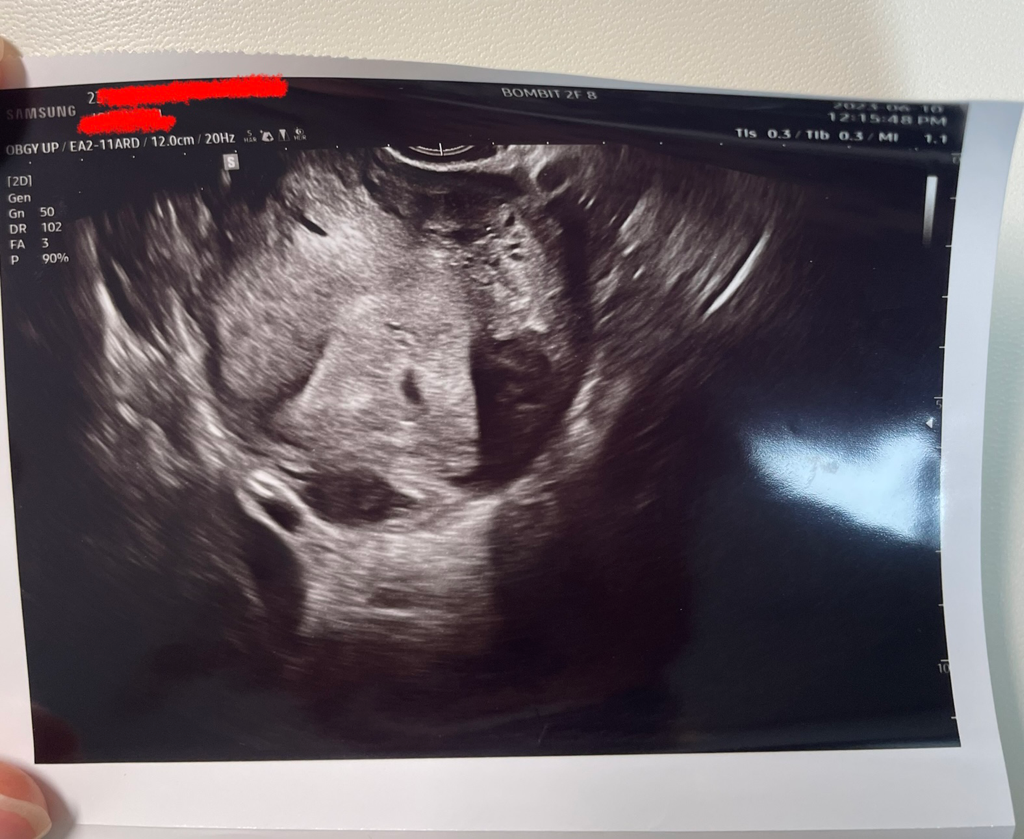

• 1번 째 사진

올려주신 초음파 사진은 아기집을 찍은 사진이라 자궁근종은 명확하지 않습니다.

첫번째 사진에서 자궁근종으로 생각되는 부분이 있어 표시해 드렸으나 직접 본 초음파가 아니며 명확히 보이지 않아 부정확합니다.